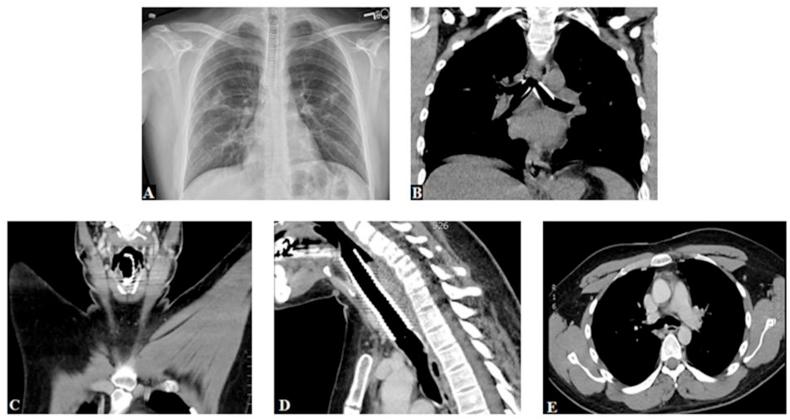

There are multiple causes of dyspnea upon exertion in young, healthy patients to primarily include asthma and exercise-induced bronchospasm. (EDAC) describes focal collapse of the trachea or main bronchi with maintained structural integrity of the cartilaginous rings. It is commonly associated with pulmonary disorders like bronchiectasis, chronic obstructive pulmonary disease and asthma. It is believed to result secondary to airway obstruction in these conditions. While uncommon in young, healthy adults, it has recently been found as a cause of dyspnea in this population. Inducible laryngeal obstruction (ILO) is an umbrella term that describes an induced, intermittent upper airway impediment. While ILO is found in 10% of young patients with exertional dyspnea, it is primarily inspiratory in nature due to paradoxical closure of the glottis or supraglottis. This report highlights the presentation of a United States Army soldier who after a deployment was given a diagnosis of asthma, later found to have ILO and was subsequently diagnosed with concurrent EDAC. We follow up with a literature review and discussion of symptomatology, diagnosis, exercise bronchoscopy, and treatment modalities for both EDAC and ILO.

在年轻健康的患者中,运动性呼吸困难有多种原因,主要包括哮喘和运动诱发的支气管痉挛。气管软化(EDAC)描述的是气管或主支气管的局灶性塌陷,而软骨环的结构完整性得以保留。它通常与支气管扩张、慢性阻塞性肺疾病和哮喘等肺部疾病相关。据信,在这些情况下,它是由气道阻塞继发引起的。虽然在年轻健康的成年人中并不常见,但最近在这一人群中发现它是运动性呼吸困难的一个原因。可诱导性喉梗阻(ILO)是一个概括性术语,描述的是一种诱发的、间歇性的上气道梗阻。虽然在10%的运动性呼吸困难的年轻患者中发现有ILO,但由于声门或声门上的反常关闭,其本质上主要是吸气性的。本报告重点介绍了一名美国陆军士兵的情况,他在部署后被诊断为哮喘,后来发现患有ILO,随后被诊断为同时患有EDAC。我们通过文献综述以及对EDAC和ILO的症状学、诊断、运动支气管镜检查和治疗方式进行讨论来跟进。